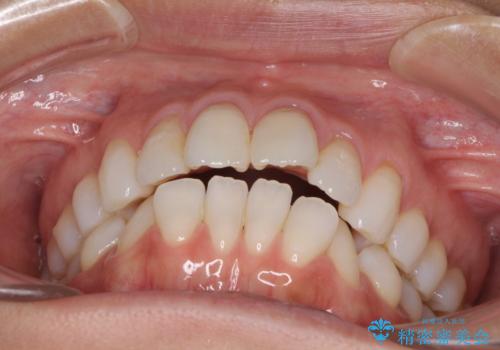

少しだけ飛び出た前歯を整えたい インビザラインによる矯正治療

- 少しだけ前に飛び出ている前歯を気にして来院された患者様です。

上顎歯列全体を後方に移動させる必要があり、インビザライン単体での治療は困難と判断し、補助装置により左右側方歯列を移動させた後にインビザラインを用いることとしました。